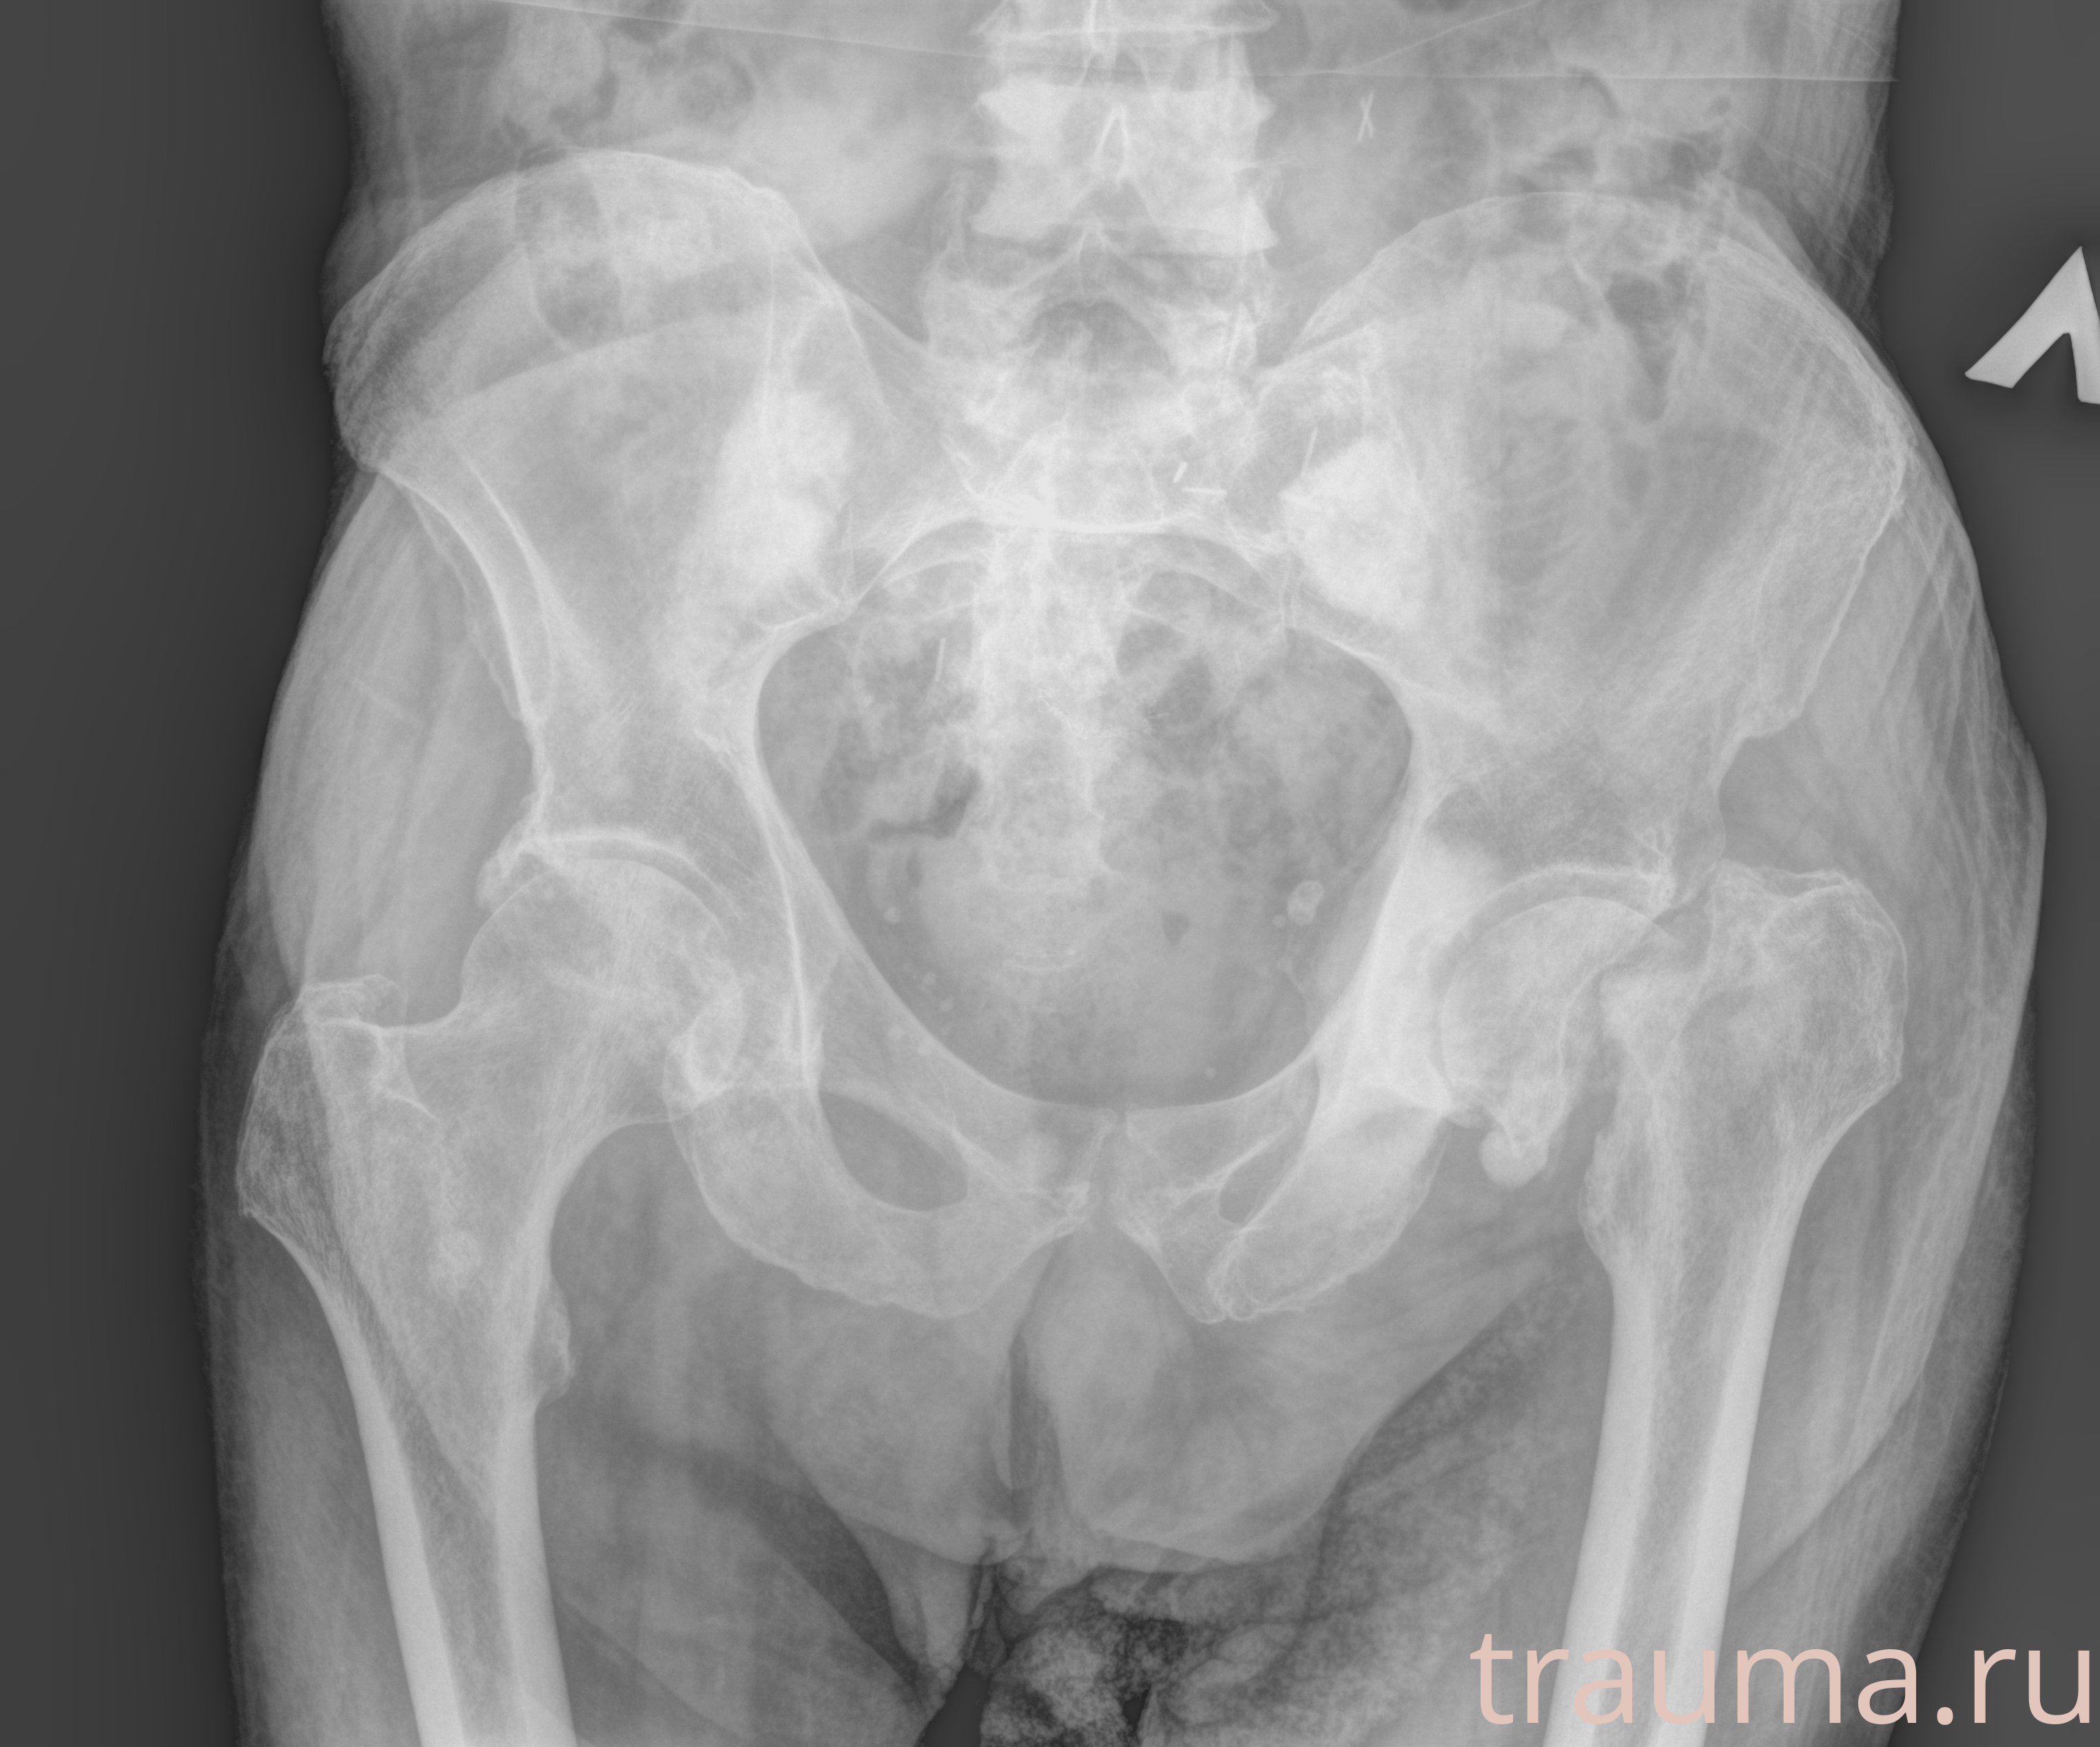

Рентгенограммы

Рентген на дому: по вашему адресу приезжает врач-рентгенолог, травматолог-ортопед с мобильным рентгеновским аппаратом, проводит диагностику травмы или заболевания, делает необходимые рентгенограммы, дает рекомендации по дальнейшему лечению. Получить качественные снимки в домашних условиях возможно благодаря уникальной методике, разработанной МосРентген Центром для института  Склифосовского